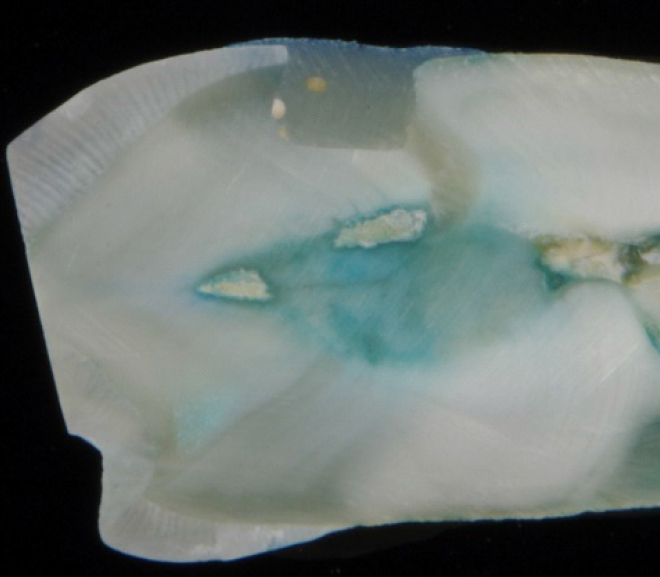

Прокрашивания в группе реставраций композитным материалом визуализируется не только по краю, но и по дну полости (рис. 3).

Рис. 3. Граница «прямая реставрация – абфракционный дефект», окрашивание после термоциклирования

Прокрашивания в группе реставраций композитным материалом кариозного дефекта произошло в меньшей степени и проявилось по краю и по стенке реставраций (рис. 4).